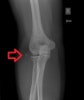

X-ray : 외상과 골절(lateral epicondyle avulsion fracture)